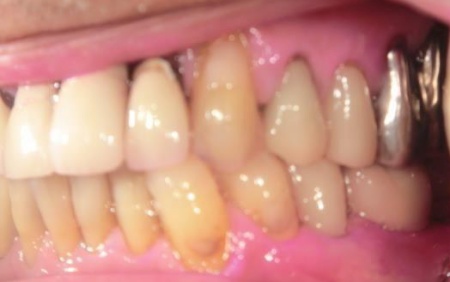

・インプラント治療

顎の骨に人工歯根を埋入し、その上から人工歯を装着する方法です。

メリット:天然歯に近い見た目や噛み心地が期待できる

デメリット:自費診療なので、ほかの治療方法に比べて費用がかかる

まず、右下奥歯(第2小臼歯)を抜き、骨が治癒するのを待ってから、インプラントを埋入します。

インプラントと顎の骨がしっかりと結合したら、精密な型取りを行い、インプラント上部に装着する最終的な被せ物を作製しました。

最後に完成した被せ物を装着し、見た目や噛み合わせに問題がないことを確認して、治療を終了しています。